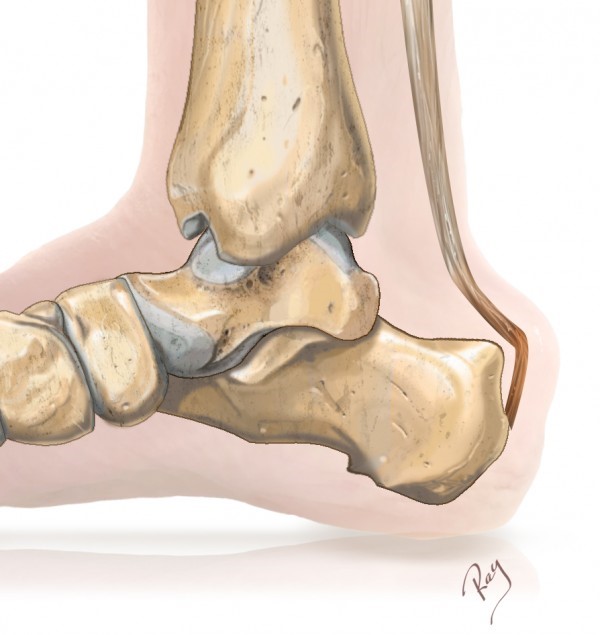

Een Haglund exostose is een verdikking van het achterste deel van het hielbeen die druk kan veroorzaken tegen de achillespeesaanhechting en de slijmbeurs tussen beide (Fig. 1-3).

Fig. 1 Fig. 2 Fig. 3